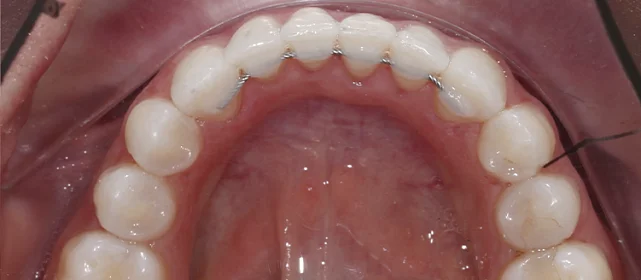

Зубы выровнены, скученность устранена. Установлены несъёмные ретейнеры на обе челюсти, сняты сканы для ретенционных кап. Ортопедия не требуется, рекомендовано лечение у терапевта.

Решение: Установили брекеты на обе челюсти. Расширили дуги, убрали скученность — всё за 15 месяцев. Визиты раз в 4–6 недель для замены дуг. После снятия зафиксировали ретейнеры на обе челюсти, сняли сканы для кап. Ортопед подтвердил, что протезирование не требуется. Терапевт рекомендовал лечение — пациентка записана.

Скученность на обеих челюстях при сужении дуг — классический случай. Зубы здоровые, корни в хорошем состоянии, мотивация у пациентки высокая. Всё это позволило уложиться в 15 месяцев без осложнений. Ортопед подтвердил, что протезирование не нужно. Рекомендовала пройти терапевтическое лечение для полного завершени